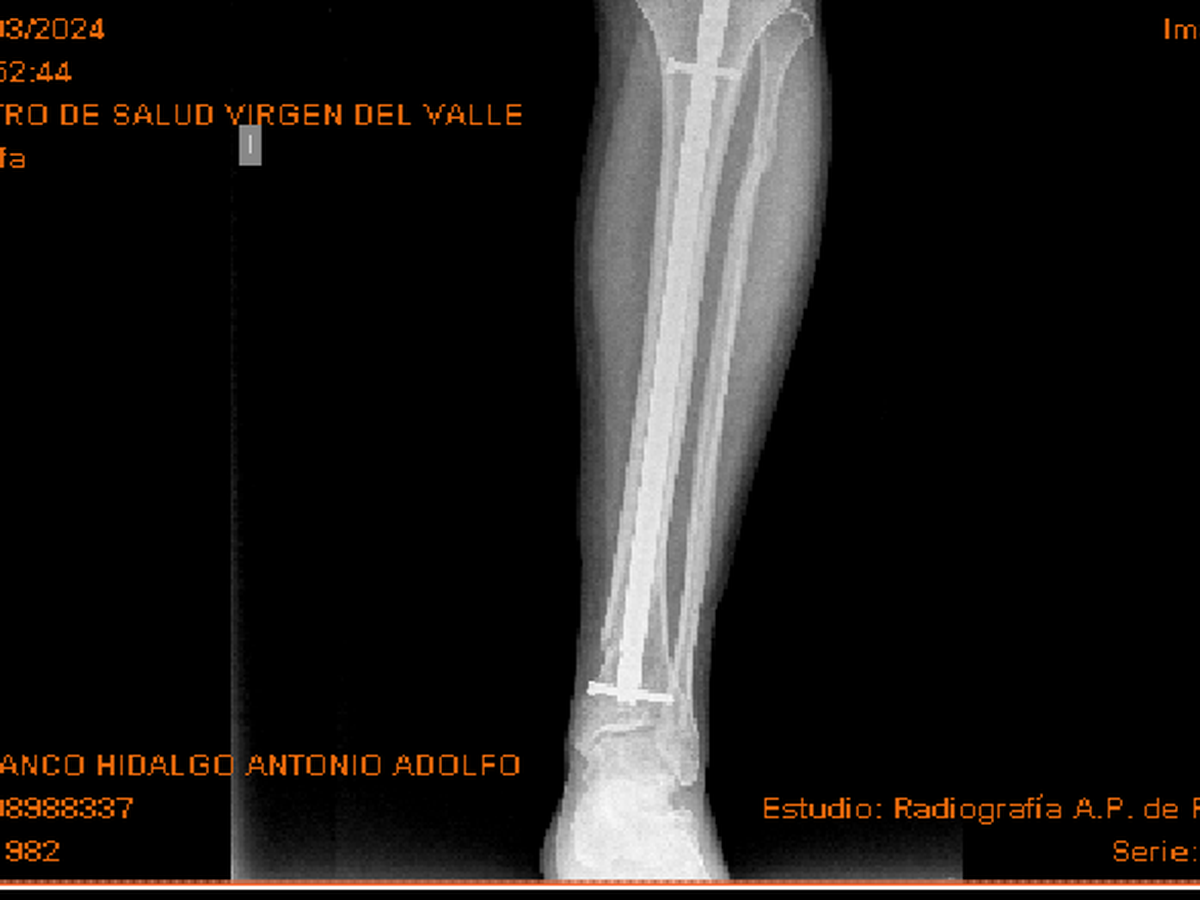

Hola, mi nombre es Antonio tengo el síndrome de asperger y también soy superviviente de maltrato infantil y me fracture la tibia y peroné hace 2 años y casi 4 meses.

Llevo casi un año que no salgo de las 2 calles continuas a mi casa. Sinceramente creo que el clavo me molesta mucho y he encontrado un traumatólogo que me quita el clavo por un precio bastante asequible.

Por recomendación de un amigo también comento que lo he intentado por la seguridad social. En principio fui a una revisión de la pierna en Barcelona donde vivía en esos momentos y me dijeron que al año y medio me lo quitaban, pero cuando pasó el año y medio por circunstancias me tuve que mudar a Andalucía y fui a la revisión de aquí de Ecija y rápidamente me dijeron que no me lo quitaban. Pedí segunda opinión en virgen del Rocío de Sevilla capital y fue muy rápido con respuesta negativa, así que mi única opción es hacerlo por privado.